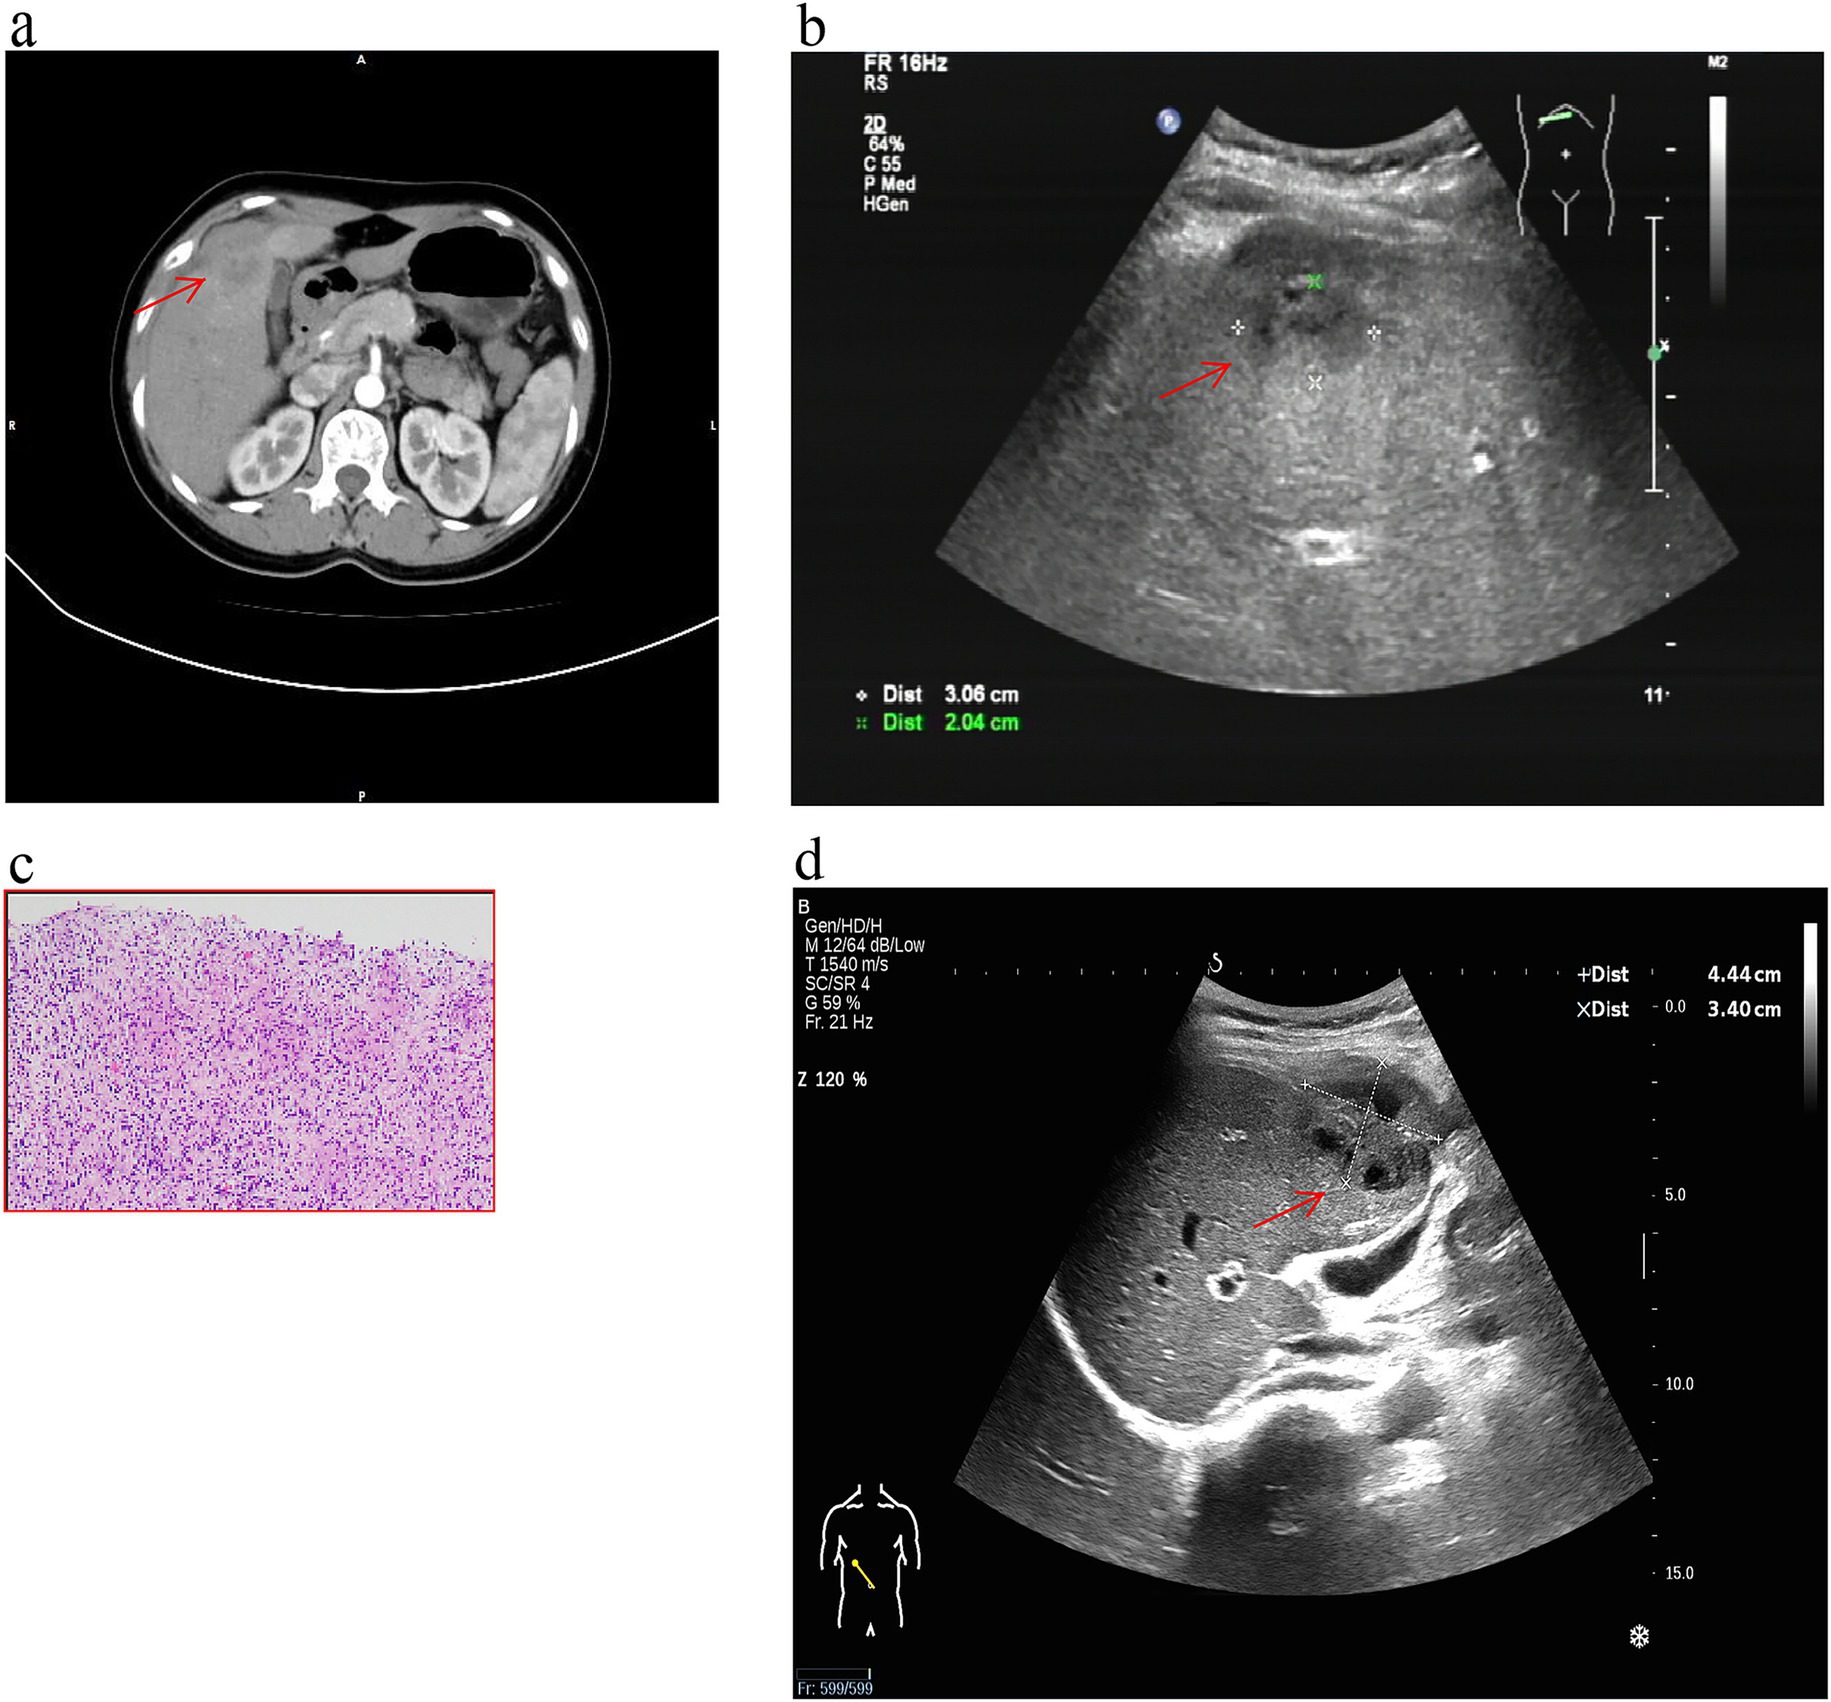

A 44-year-old woman presented with complaints of abdominal pain for the past 2 months. The patient’s abdominal pain was intermittent, lasting from several minutes to several hours. It was accompanied by a decreased appetite, fever, and night sweats. However, there were no symptoms of nausea, vomiting, changes in bowel movements, chills, or cough with sputum production. The patient was born and currently resides in Luzhou City, Sichuan Province, China. She is a company clerk and denies any history of contact with animals or tuberculosis. She also reports no past medical history of liver disease, tuberculosis, or acquired immune deficiency syndrome (AIDS). In the past year, she had not experienced any weight loss or traveled outside of Luzhou. She was dyspneic (RR = 20 breaths/min), had a temperature of 36.5 °C, a heart rate of 70 beats per minute, blood pressure of 118/78 (normal range, 60–90/90–140) mmHg, and a 33% oxygen saturation on room air at the time of admission. Abdominal examination revealed periumbilical and right lower abdominal wall tenderness and rebound pain. The rest of the system examination was unremarkable. The chest computed tomography (CT) was normal. The contrast-enhanced abdominal CT scan shows a small amount of ascites in the lesser omentum sac and the abdominal and pelvic cavities, with the pelvic cavity being the main site. The greater omentum, mesentery, and peritoneum are extensively thickened, with some areas showing nodular thickening. These are all manifestations of tuberculous peritonitis. The contrast-enhanced CT also reveals a round, low-density, non-enhancing shadow in the right anterior lobe of the liver, with a diameter of approximately 0.8 cm. There is a patchy enhancement in the left medial lobe of the liver during the arterial phase, and the enhancement is consistent with the surrounding liver parenchyma during the venous phase. The hepatic CT showed an irregular mass of approximately 4.1 cm × 3.1 cm in the right anterior space of the liver, part of which invaded the right anterior lobe of the liver (Figure 1a). The findings are consistent with an infection complicated by abscess formation involving the anterior segment of the right hepatic lobe. The right lobe of the liver’s ultrasound revealed a cystic dark region measuring 3.7 cm × 2.1 cm (Figure 1b). To confirm the diagnosis, we performed a liver biopsy (4). Ultrasound-guided biopsy of the lesion was done, which showed chronic granulomatous inflammation suggestive of tuberculosis (Figure 1c). The tuberculin test was positive. TB-DNA real-time PCR performed on the aspirated pus was positive, confirming the presence of M. tuberculosis complex DNA. Her total leucocyte count was 7.01 (normal range, 3.5–9.5) × 109/L, neutrophil count was 5.56 (normal range, 1.8–6.3) × 109/L, platelet count was 229 (normal range, 100–350) × 109/L, C-reactive protein (CRP) level was 10.65 mg/L, and erythrocyte sedimentation rate (ESR) was 33 mm3. The renal function and electrolyte tests showed urea, 5 (normal range, 3.1–8.0) mmol/L; uric acid, 231 (normal range, 208–428) μmol/L; glomerular filtration rate, 100 (normal range, ≥90) mL/min; creatinine, 72 (normal range, 57–97) μmol/L; potassium, 4.15 (normal range, 3.5–5.3) mmol/L; sodium, 140 (normal range, 137–147) mmol/L; and chloride, 105.2 (normal range, 99–110) mmol/L. The liver function tests showed alanine aminotransferase, 80 (normal range, 9–50) U/L; aspartate aminotransferase, 78 (normal range, 15–40) U/L; total bilirubin, 17 (normal range, 0–26) U/L; direct bilirubin, 8.6 (normal range, 0–8) U/L; indirect bilirubin, 8.4 (normal range, 0–20) U/L; and albumin, 35 (normal range, 40–55) g/L. Blood culture was negative. The carcinoembryonic antigen, CA-19.9, CA-125, and a-fetoprotein serum tumor markers were all within normal limits. The HIV test was negative. She was diagnosed with hepatic tuberculosis and tuberculous peritonitis. Anti-tuberculous medication (isoniazid, rifampin, ethambutol, pyrazinamide) was initiated for the patient. The abscess’s size had increased on the abdominal ultrasonography performed 1 month after the diagnosis (Figure 1d). Abdominal ultrasound revealed a 4.4 cm × 3.4 cm area of heterogeneous echogenicity in the anterior segment of the right hepatic lobe, with ill-defined borders, hypoechoic areas, and internal septations. After discharge, the patient continued to be managed and followed up as an outpatient, but she took herself to a specialized infectious-disease hospital immediately after this repeat ultrasound. During the subsequent period, telephone follow-up indicated that the patient continued anti-tuberculosis therapy (the specific regimen was not documented), with symptoms gradually improving and essentially resolving after 6 months.

Figure 1

Rare case of tuberculosis liver abscess. (a) The abdominal hepatic CT scan revealed a single, well-defined focal lesion measuring 0.8 cm in the low-density area of the right liver lobe and an irregular mass measuring approximately 4.1 cm × 3.1 cm in the right anterior space of the liver (red arrow). (b) Ultrasound of the abdomen showed a cystic dark area of 3.7 cm × 2.1 cm in the right posterior lobe of the liver (red arrow). (c) Hematoxylin–eosin staining shows chronic granulomatous inflammation suggestive of tuberculosis (HE ×200). (d) The abdominal ultrasound reveals a noteworthy enlargement of the abscess, measuring 4.4 cm × 3.4 cm (red arrow).